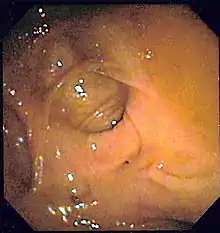

| A positive fecal occult blood test | |